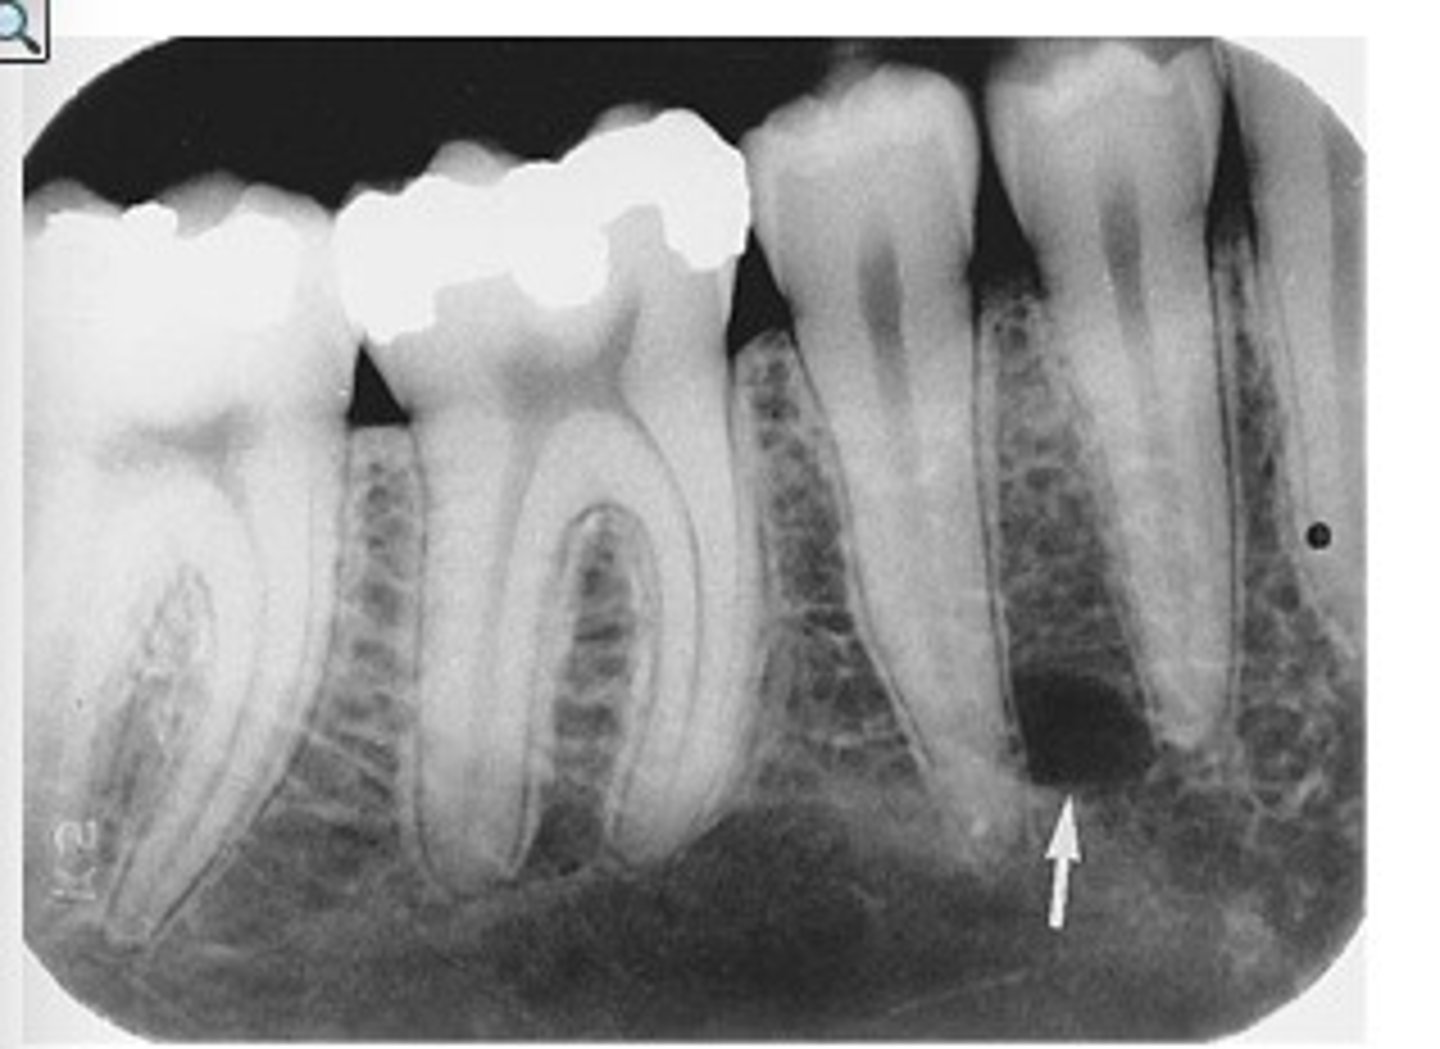

Does chronic abscess appear radiopaque or radiolucent?

Radiolucent

What condition is not visible on an inter proximal radiograpgh

Apical Abscess